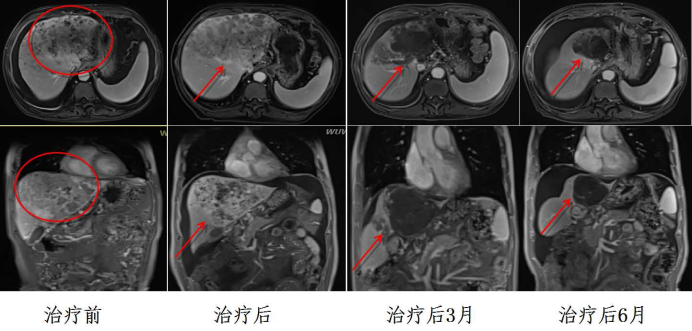

Efficacy comparison

Following discharge, Mr. Du underwent hospital-based re-evaluations every three months as medically advised. Remarkably, imaging surveillance demonstrated progressive shrinkage of his hepatic mass, with near-complete radiological resolution observed at the 6-month post-carbon ion therapy interval. Notably, regenerating hepatic parenchyma was identified in previously involved zones—a phenomenon likened by his family to "spring sunshine dissolving winter's gloom," symbolizing their renewed hope.

At this critical juncture, a fellow patient's recommendation led Mr. Du to discover the team of Prof. Wang Junjie, Chief Physician at Lanzhou Heavy Ion Hospital. Through peer connections, he consulted with Director Li Xiaojun of the Carbon Ion Radiotherapy Group, who provided detailed online guidance on subsequent treatment protocols. Determined to pursue this final beacon of hope, Mr. Du resolved to travel northwest despite having only 600 mL of functional liver parenchyma remaining—a condition rendering conventional radiotherapy prohibitively risky due to >70% mortality risk from acute radiation-induced hepatitis. Viewing heavy ion therapy as his last therapeutic lifeline, Mr. Du courageously opted for this innovative modality. In August 2023, he journeyed from Shanxi to Gansu Province. Following a multidisciplinary team (MDT) consultation at the Heavy Ion Center, clinicians confirmed his eligibility for carbon ion radiotherapy. Director Li Xiaojun's team meticulously optimized treatment parameters: customized positioning protocols, respiratory motion compensation, beam angle optimization. This precision planning achieved maximal hepatic parenchymal sparing during dose distribution evaluation. Mr. Du completed 18 fractions of hepatocellular carcinoma-targeted carbon ion therapy, supplemented with concurrent immunotherapy and targeted agents. Throughout treatment, President Wang Junjie's team implemented rigorous hepatic function monitoring and nutritional interventions. Remarkably, Mr. Du experienced no significant radiation toxicity, with progressive clinical improvement documented. In his own words: "Like spring shoots emerging from withered wood, this breakthrough technology revived my hope."